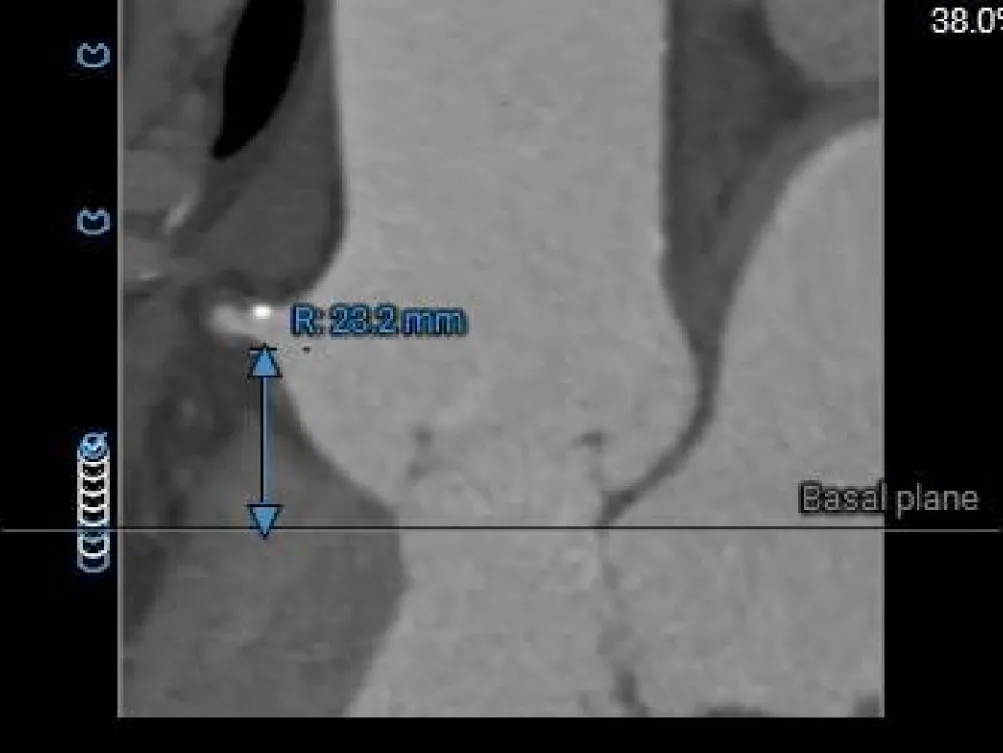

左冠开口高度约为25.2mm,右冠开口高度约为23.2mm;